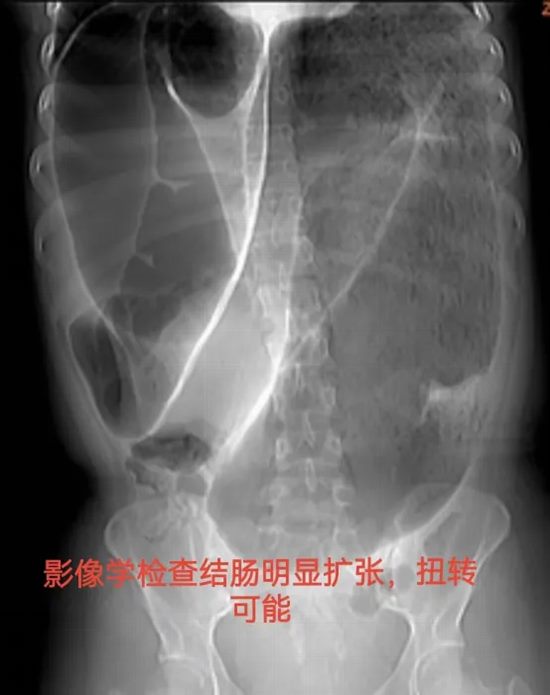

病情简述:19岁女性,间断腹痛腹胀4年,辗转求医未果。此次因急性加重急诊入院。

诊疗破局:CT提示结肠梗阻,非手术减压无效。急诊剖腹探查发现元凶是罕见的“结肠重复畸形”并扭转。及时的手术不仅解除了急性梗阻,切除了病变肠段,更找到了困扰她4年的病根。术后患者恢复良好,已回归正常生活。